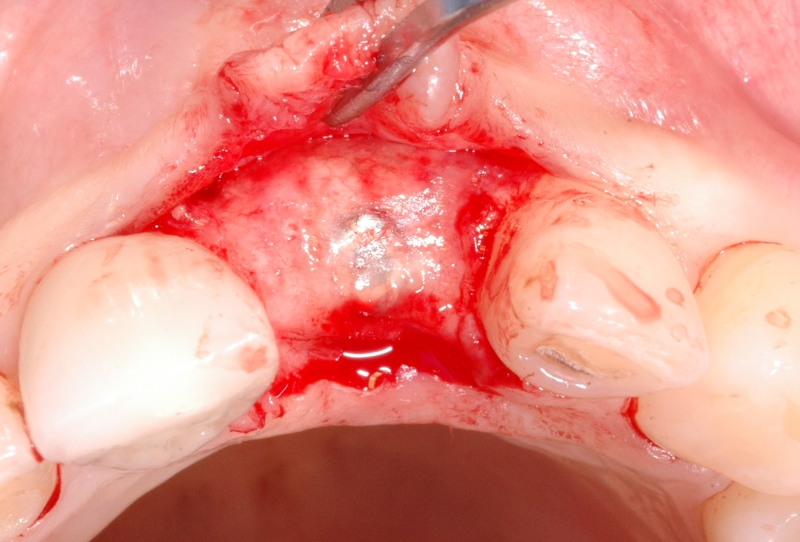

5/18 - Situation after implantation showing a buccal defectGBR together with soft tissue augmentation with mucoderm® and maxresorb® - Dr. S. Scherg